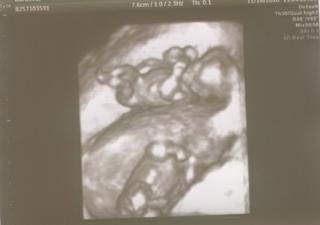

Jinak ten utz včera byl moc hezkej, manžel byl nadšenej jak sebou jen prcek krásně házel, ani nešel pořádně

změřit 😀 dr. říkal, že jsou v pořádku, tak snad bude všecho ok. i v tom 20týdnu.